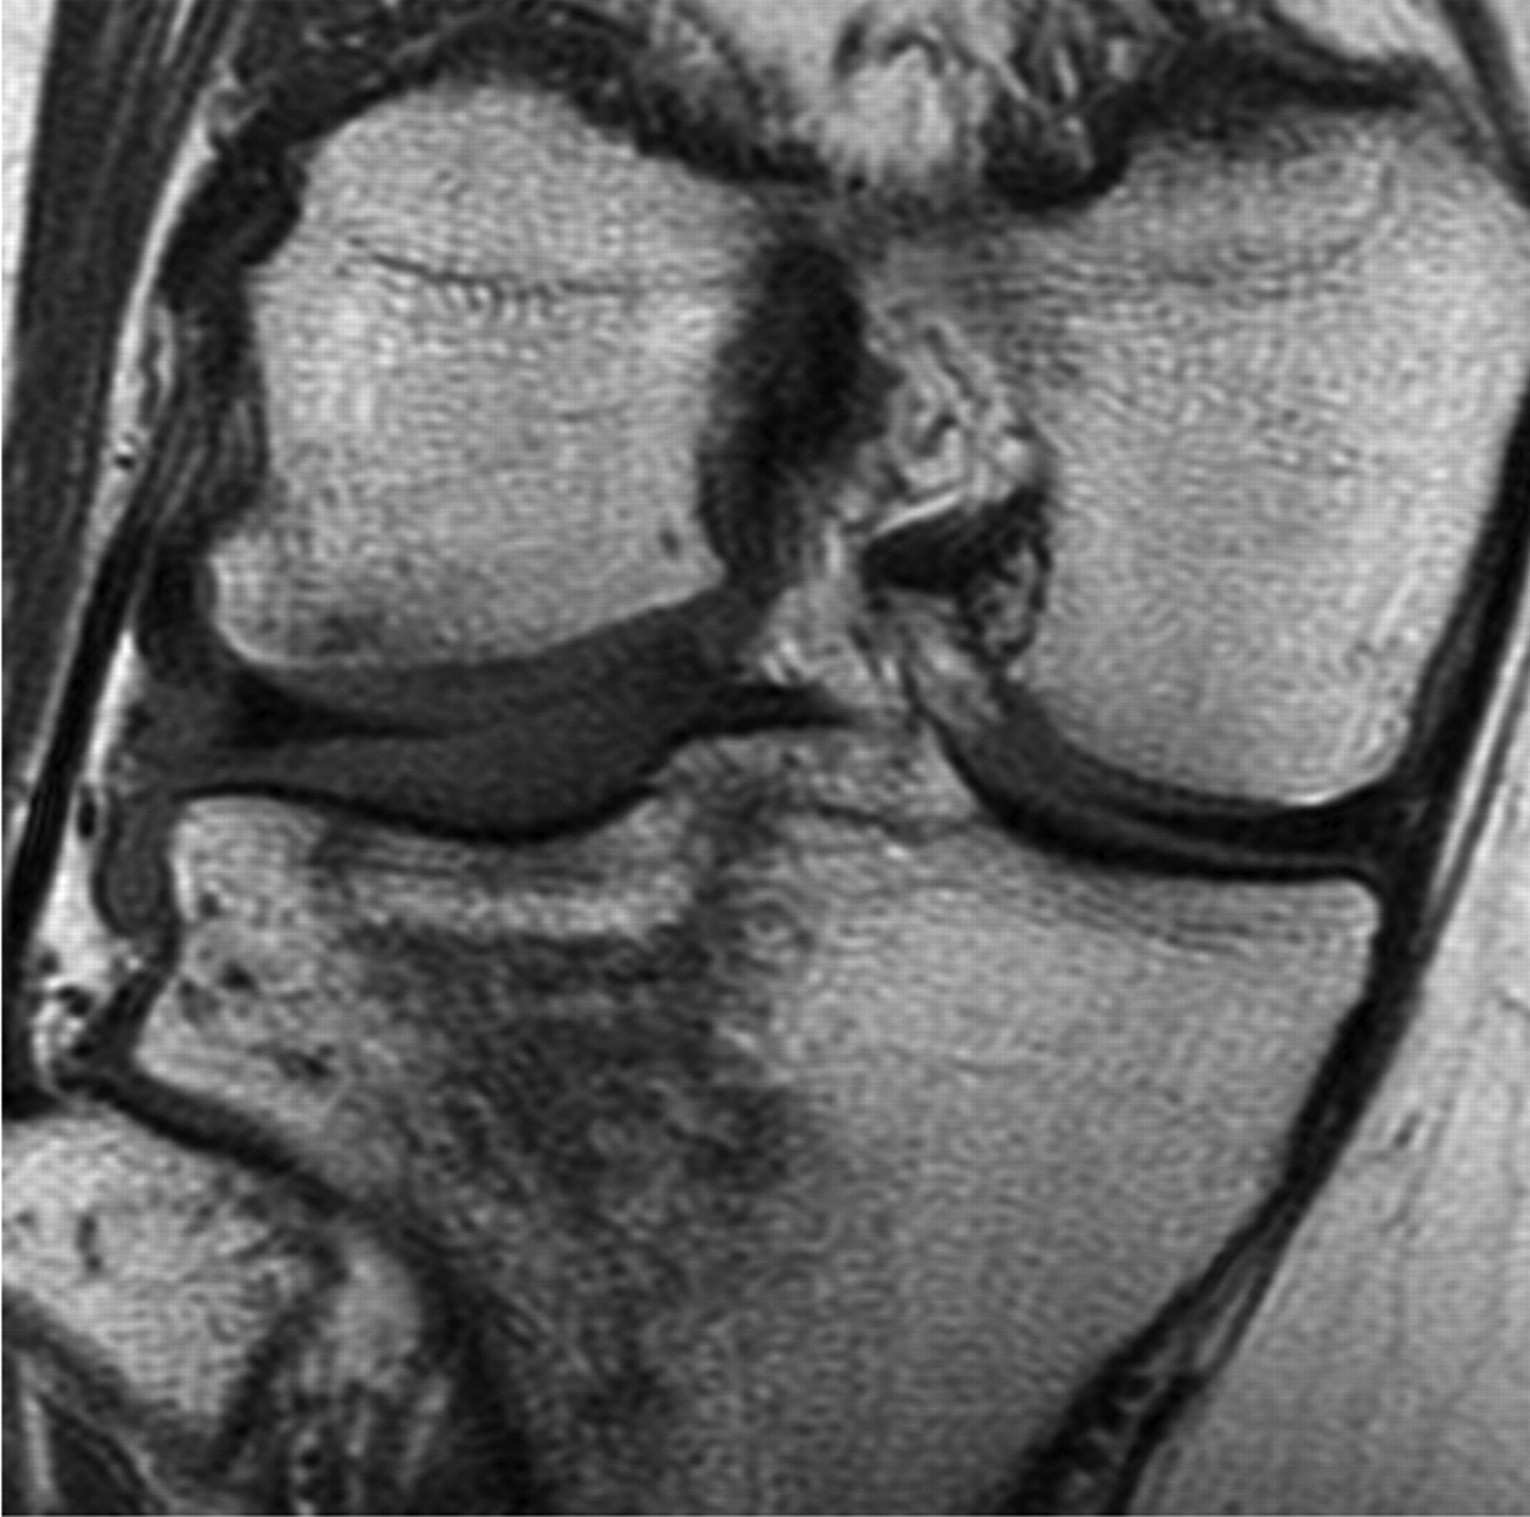

Some subtle injuries where the bone is marginally impacted are only identified on CT or MRI.